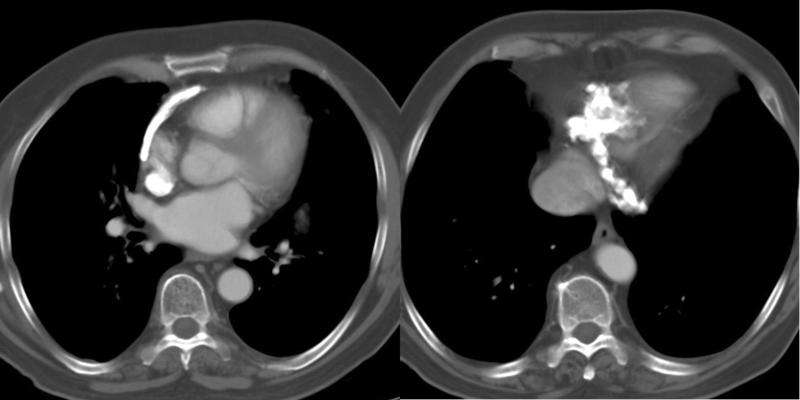

Peric calcification